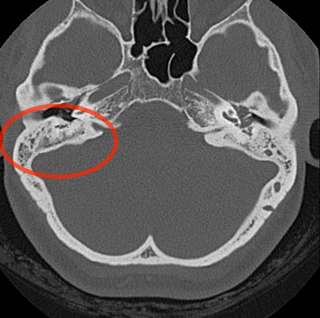

Подозрение на холестеатому является одним из самых частых показаний для КТ височных костей. Диагноз устанавливается при осмотре, КТ служит только для уточнения степени распространения процесса. Только в редких случаях с помощью КТ можно однозначно установить диагноз. На рисунке ниже показаны аксиальный и фронтальный срезы КТ височной кости с холестеатомой. Четко определяется эрозия костной ткани, что является основным признаком холестеатомы. Другим признаком является эрозия ушной капсулы. Деструкция слуховых косточек может встречаться и при простом хроническом среднем отите, поэтому ее нельзя рассматривать как признак холестеатомы.

Н, ниша круглого окна; I, латеральный полукружный канал; J, нисходящий сегмент лицевого нерва. КТ височной кости в (а) аксиальной и (б) фронтальной проекциях,

на которой определяется холестеатома, расположенная латеральнее молоточно-наковального сустава, разрушающая скутум.

Приобретенная холестеатома представляет собой кератиновые массы, способные вызвать воспаление и инфицирование тканей. В среднем ухе обнаруживается мягкотканное содержимое, возможна деструкция сосцевидных ячеек височной кости или структур внутреннего уха. Наиболее часто холестеатома локализуется в области ненатянутой части барабанной перепонки, т.е. в пространстве Пруссака, между скутумом и наковальней.

На КТ отмечается присутствие мягких тканей в пространстве Пруссака, но их наличие само по себе не является достаточно специфичным признаком. В то же время обширный деструктивный процесс может захватывать цепь слуховых косточек, вызывая ее разрыв, или приводить к эрозии скутума.

На КТ-холестеатома имеет вид мягкотканого образования с сопутствующими костными эрозиями.

Томографические признаки холестеатомы: